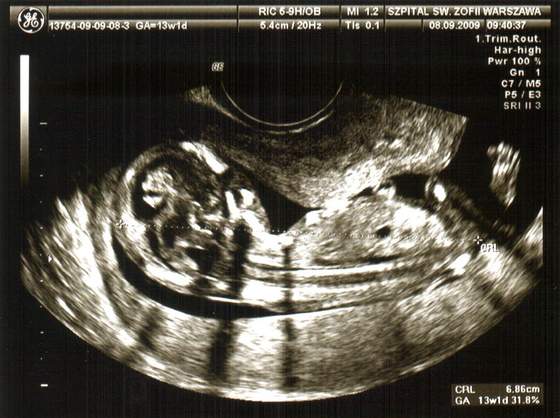

Muszę się pochwalić - wczoraj byłam na USG, czyli w ostatnim dniu 13 tygodnia. Dzidziuś wielki, bo mierzy 8,88cm i Pan doktor powiedział ,że wg. niego to ewidentnie jest chłopiec. Byłam zdziwiona ponieważ nie spodziewałam się w tym momencie, że będzie już coś widać.Dzidziuś jest zdrowy i to jest najważniejsze